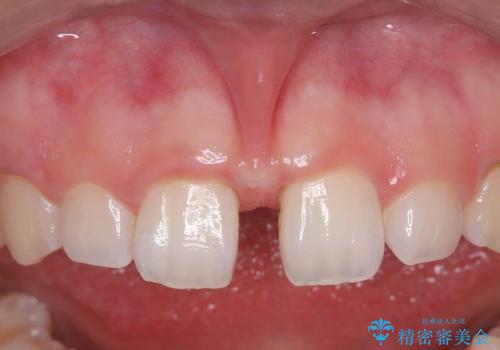

【上唇小帯切除術】子どもの頃から上の前歯の歯茎が気になってた!

担当医 河野豊嘉